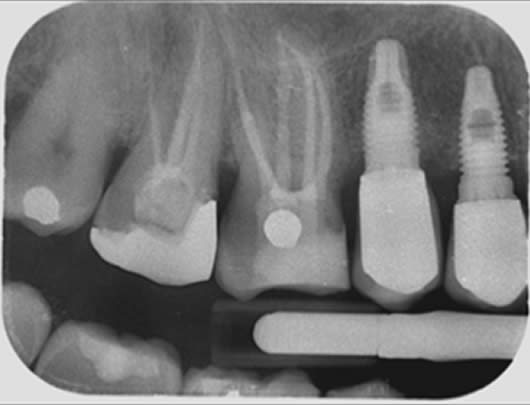

Case 3: Root canal treatment – narrow canals.

As a tooth ages, whether prematurely following trauma or long-term irritation, or in accordance with natural ageing, the root canals can become narrower due to the laying down of further dentine (tooth structure). This can make the canals difficult to locate and very challenging to negotiate to full length. As with finding the elusive MB2 canal (Case 2), we use our experience and the use of the dental microscope to conservatively remove tooth tissue in just the right areas to locate these canals. This cases shows a tooth (UL6) in which it is difficult to see the canals on the radiograph as they are very narrow. We were able to locate four canals (including the challenging MB2 canal) and prepare and fill them.

Before treatment UR6

Following root canal treatment UR6